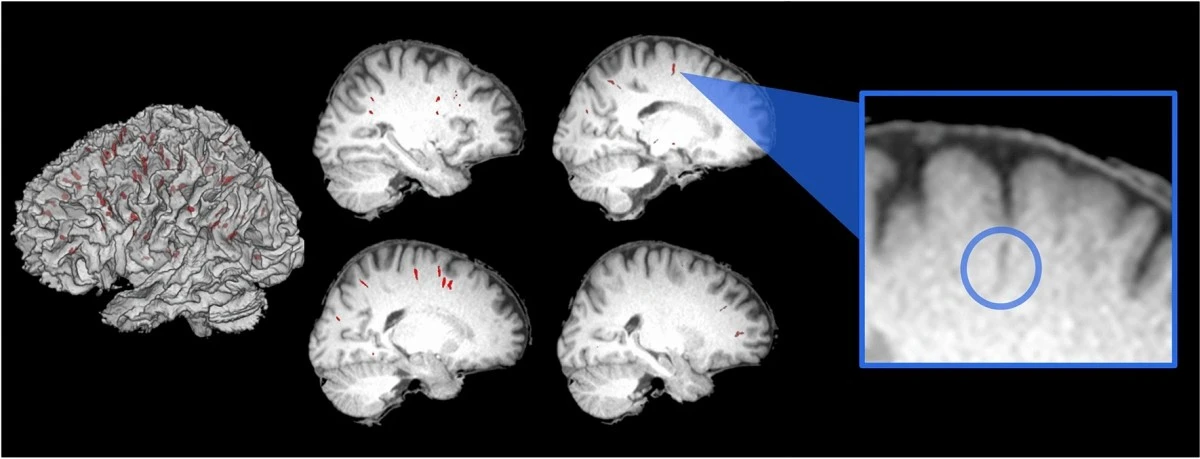

W ramach badania porównano wyniki rezonansu magnetycznego mózgu 15 astronautów wykonanego na sześć miesięcy przed podróżą na Międzynarodową Stację Kosmiczną oraz do sześciu miesięcy po powrocie ze stacji. Dokładniej mówiąc, w swoim badaniu naukowcy przyjrzeli się przestrzeniom otaczającym naczynia krwionośne znajdujące się wewnątrz mózgu. Wykorzystując algorytmy, by precyzyjnie określić rozmiary tych przestrzeni, odkryto, że czas spędzony w kosmosie ma znaczący wpływ na unaczynienie mózgu, a przynajmniej u osób, które doświadczyły pierwszego pobytu na ISS.